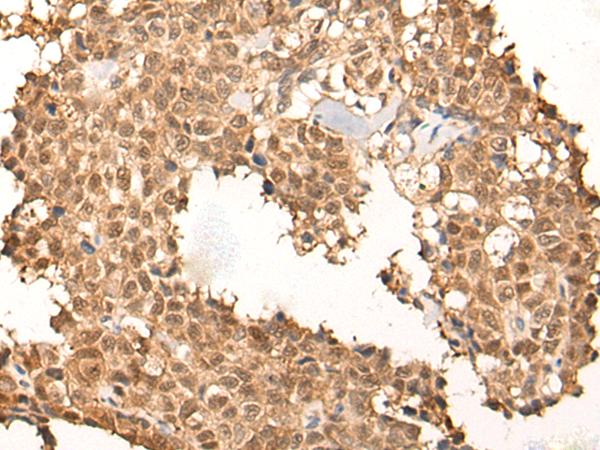

IHC positive control: |

Human thyroid cancer and human ovarian cancer |